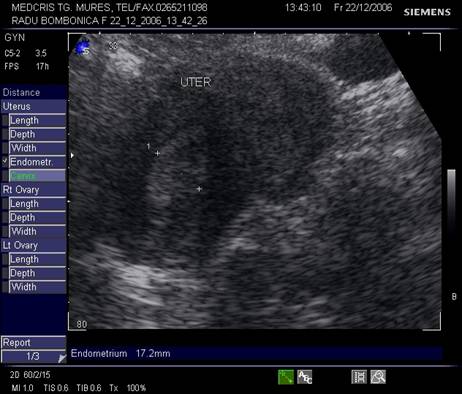

Fig. nr.352. Uter in retroversoflexie , cu hiperplazie de endometru la ecografia abdominala.

Endometrul - grosimea sa este apreciata in sectiune longitudinala. Masurarea se va face de la interfata miometru - endometru la interfata identica, opusa, de pe peretele celalat uterin. Maxim acceptat normal este de 1,5 cm in perioada de premenopauza.[5] Postmenopauza in mod normal nu depaseste 5 mm, de obicei este atrofic si apare ca o imagine ecogena lineara. Daca apare o colectie anecogena postmenopauzala intrauterina, prin atrofie cervicala, aceasta colectie nu trebuie sa fie masurata la calculul grosimii endometriale.[2,6]